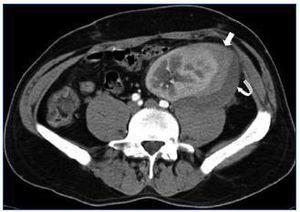

Se realizó una ecografía-Doppler de urgencia que informaba injerto en fosa ilíaca izquierda (FII) de 121 mm con aumento de la ecogenicidad cortical, buena perfusión, IR: 1, identificándose una colección organizada perirrenal de 93 x 37 x 60 mm que se interpretó como un hematoma. Para completar el estudio se realizó una tomografía computarizada con contraste que mostró realce de todo el riñón con dos imágenes lineales hipoecoicas, que se interpretaron como fractura del polo inferior del injerto (figura 1 y figura 2). No se observaron imágenes de aneurisma ni de tumor renal. Ante la estabilidad hemodinámica y el diagnóstico de ruptura renal evolucionada se descartó tratamiento quirúrgico urgente. Se realizó una primera sesión de hemodiálisis; coincidiendo con ésta presentó reanudación de la diuresis en 48 h con progresiva mejoría de los parámetros analíticos. Se descartó el diagnóstico de RA dada la evolución favorable del paciente sin haber tomado otras medidas terapéuticas y que tenía los niveles de inmunosupresores en rango.

Figura 2. Tomografía computarizada del injerto que muestra dos imágenes lineales hipoecoicas compatibles con fractura del polo inferior (flechas finas).